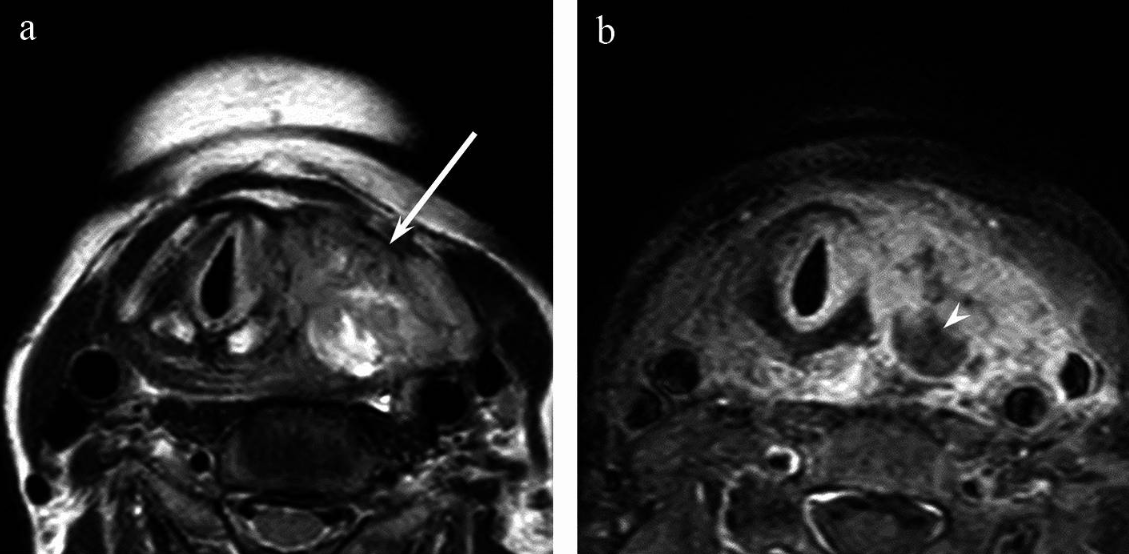

The solid components of anaplastic thyroid carcinoma frequently show hyperintensity on T2-weighted images compared to the spinal cord17. It also often presents with ill-defined margins and shows a higher incidence of extension out of the thyroid, tracheal, and oesophageal invasion, vascular invasion, and venous thrombosis, reflecting their aggressive nature.

MRI accurately detects extrathyroidal extension, which means the tumour has spread beyond the thyroid gland itself into surrounding tissues like muscle or fat1,15. This finding signifies a more advanced or aggressive disease and affects treatment plans significantly.

MRI can clarify whether cancer is invading key structures near the thyroid, such as the windpipe, nerves, and major blood vessels, which is critical for surgical planning and prognosis1,16.